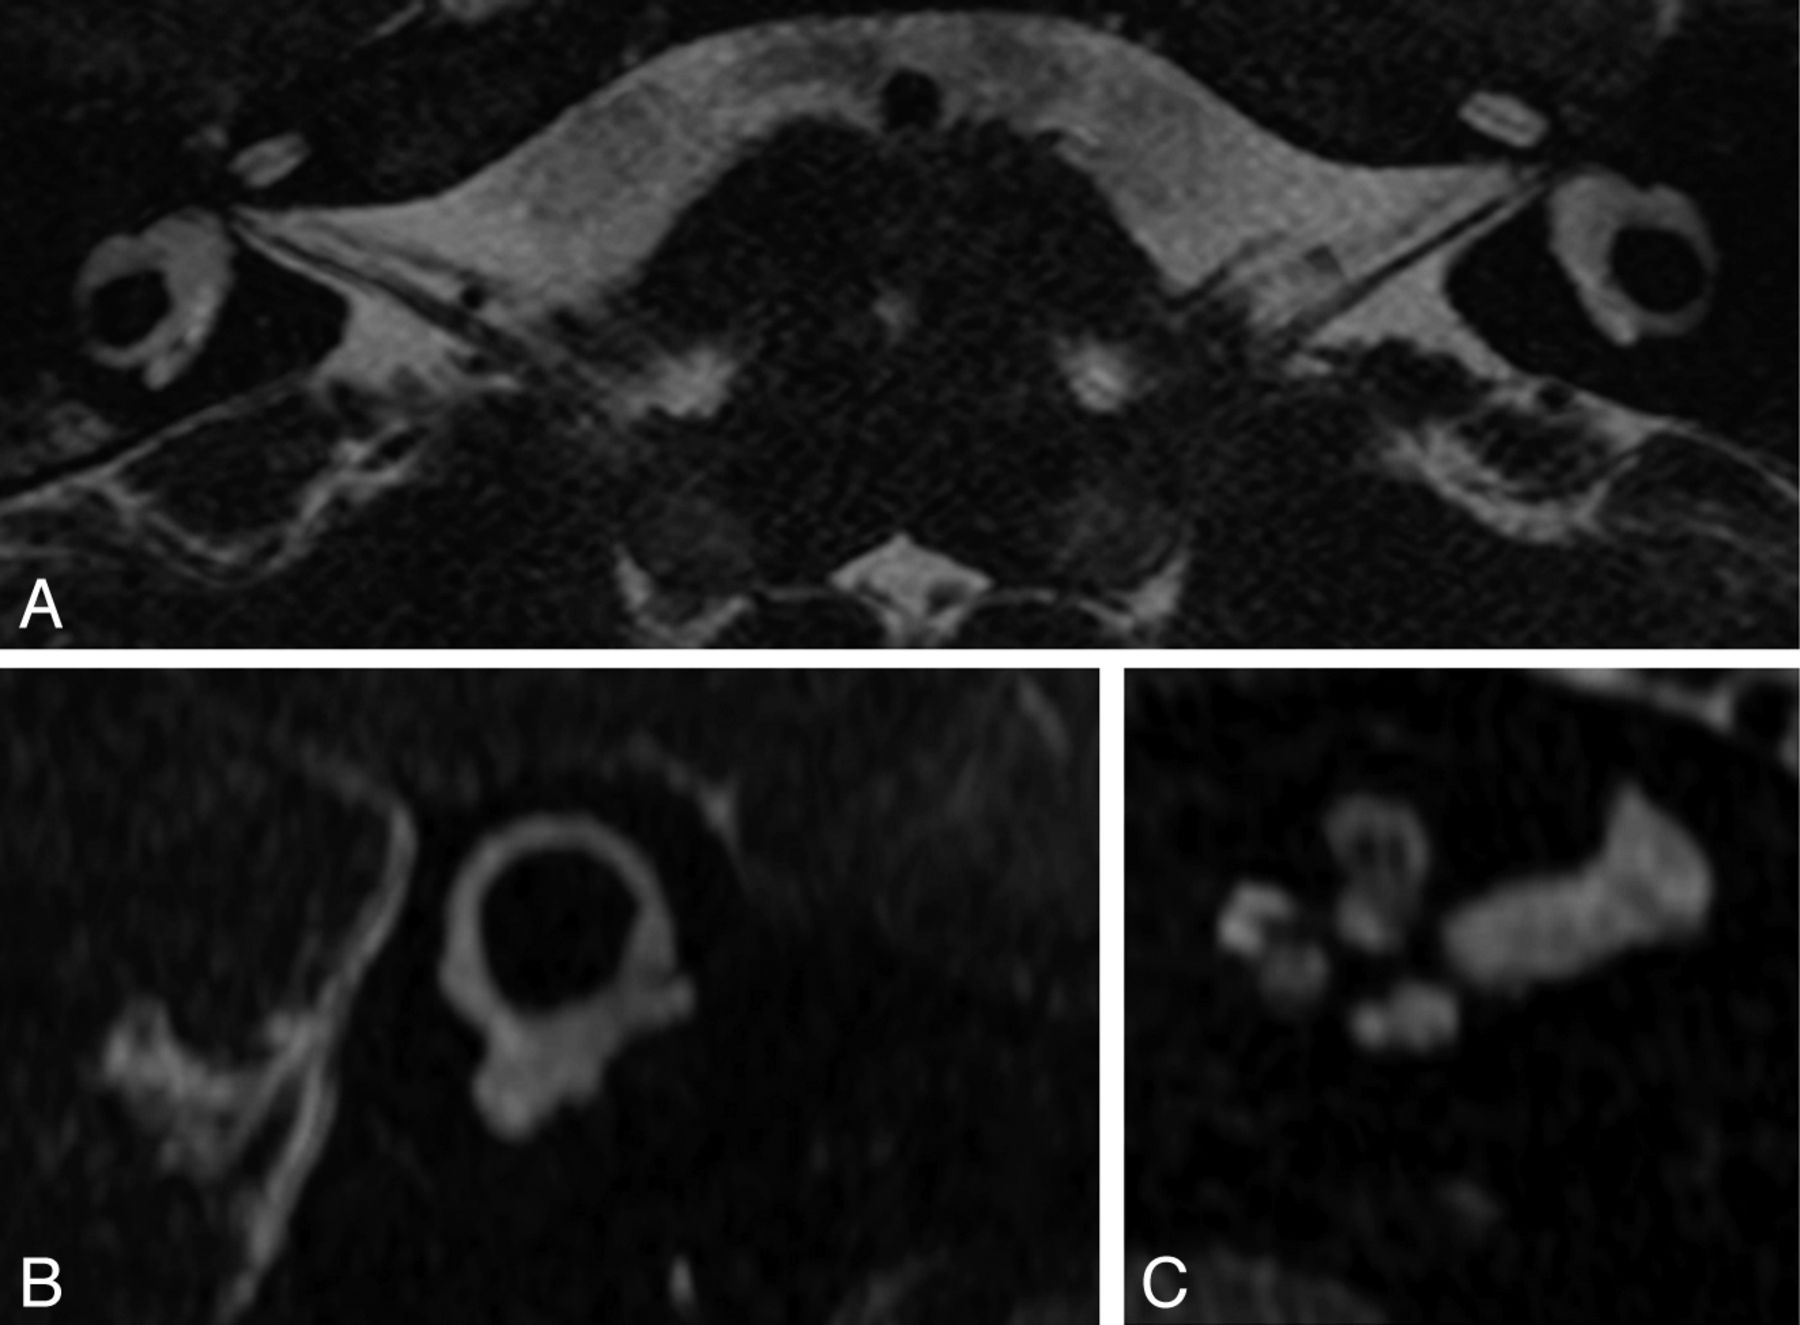

Patient H. High-resolution 3D T2 MR imaging. Axial views through the cochlea and lateral SCC show a cochlea reduced in size with a flattened aspect of the midturn and apex; an enlarged vestibule; and a lateral SCC with a small diameter, a thin arch, and a small bone island. The basal turn was normal in this patient (not shown). The left cochlea is thinner than the right; this finding was confirmed by oblique sagittal views perpendicular to the nerves (not shown).

Patient B. 3D T2 TSE MR image driven equilibrium (Philips). Reformatted axial view in the lateral SCC plane (A) and maximum intensity projection of the superior and posterior SCC (B and C). Same patient as in Fig 2C. Axial view shows a short linear structure along the posterior aspect of the lateral SCC, but multiplanar reformations and maximum intensity projection demonstrate a deformity of the posterior aspect of the vestibule and no posterior SCC. The superior SCC has a thin arch with a large diameter. Hypersignal of the inferior cerebellar peduncles is noticeable due to hypomyelination.